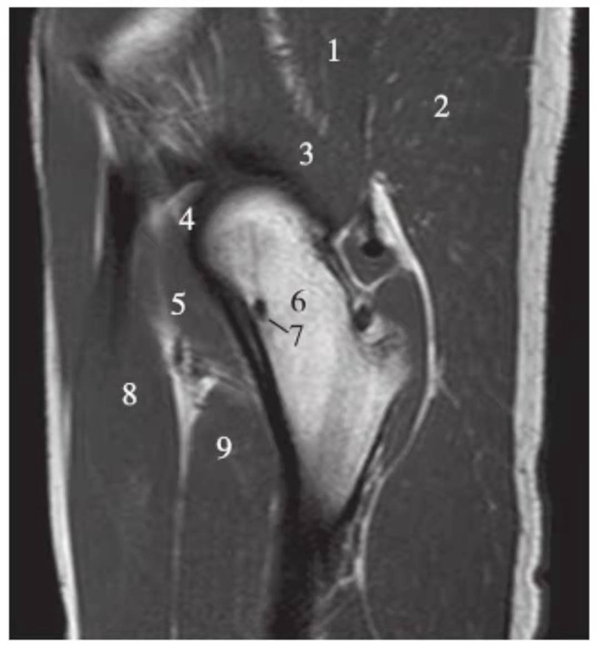

正常髋关节经股骨头外缘层面T1WI像

1.臀中肌;2.臀大肌;3.臀小肌;4.关节囊及髂股韧带;5.髂腰肌;6.股骨颈;7.骨岛;8.股直肌;9.股中间肌